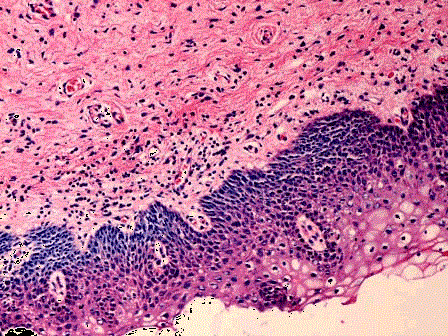

问题 女性,34岁,阴道分泌物增多并有异味,检查宫颈肥大,质硬,宫颈黏膜中度-重度糜烂,取宫颈黏膜活检,显微镜下如图。应诊断为 ( )

选项 A.慢性宫颈炎 B.宫颈息肉 C.CINⅠ D.CINⅡ E.宫颈原位癌

答案 A